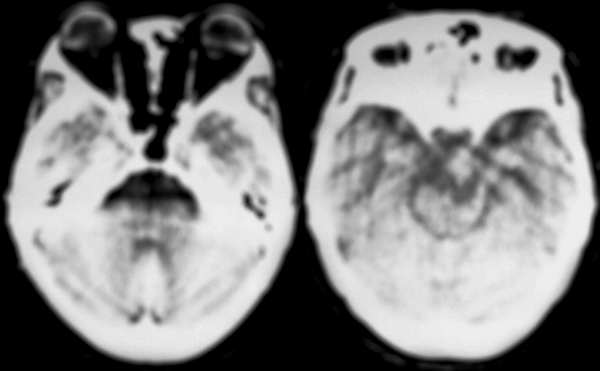

ct扫描显示:中线部位鞍上可见一圆形低密度病变,边缘清晰,密度尚均匀,ct值与脑脊液相仿,囊内左后是点状钙化影,病变向下葡行生长至脚间池,脑干受压变形;脑室系统未见明显异常.

诊断意见:鞍上囊性占位性病变,多考虑表皮样囊肿.

颅咽管瘤

在胚胎期,rathke囊与原始口腔连续的细长管道称颅咽管,应退化消失,但可残留一些鳞状上皮细胞,颅咽管瘤即起源于这些残留的上皮细胞,亦有人认为是垂体腺细胞的上皮化生。任何年龄均可发病,半数发病年龄小于20岁,另一高发年龄为40~60岁。

ct表现:鞍上区圆形、类圆形、不规则肿块,密度随成分差异较大,亦完全囊变和部分囊变多见,一般呈脑脊液样密度,也可因含较多胆固醇呈很低密度,含钙质、蛋白质呈稍高密度,也可完全实性。钙化率高,可沿边缘呈壳状,实质部分可呈点状、斑片状、不规则团块状。